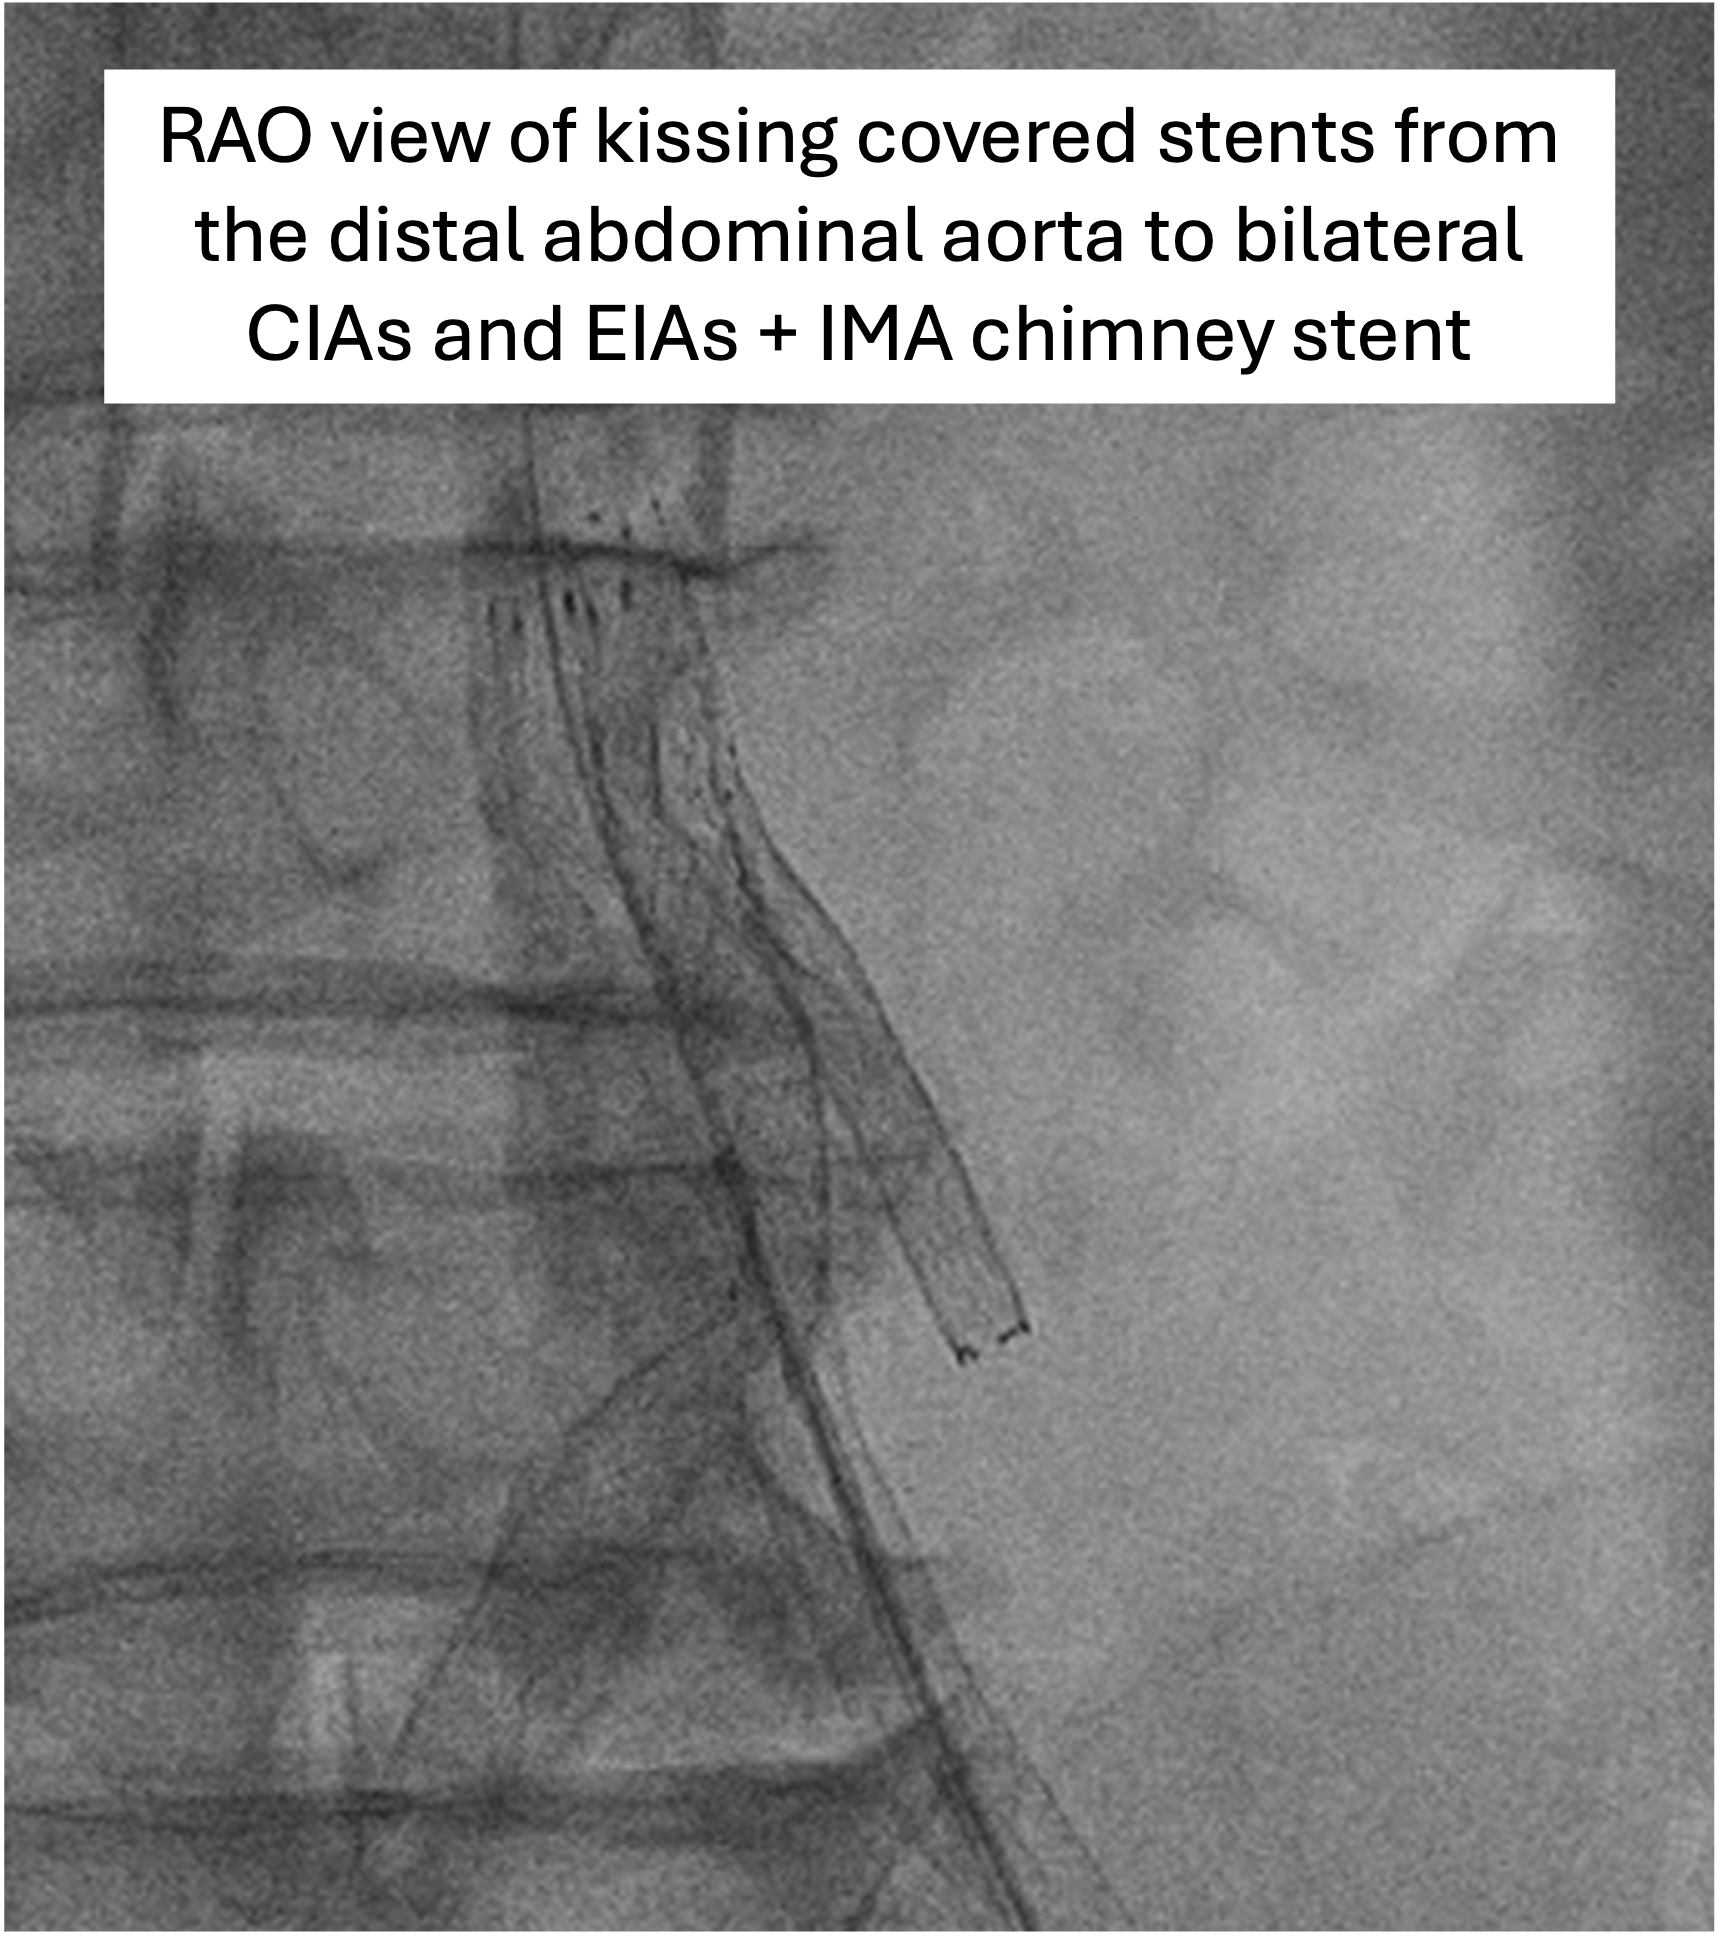

The Vascular team performed aortoiliac revascularisation to concurrently treat his peripheral vascular disease and allow for femoral access for CHIP. Kissing covered stents were placed from the abdominal aorta to bilateral CIAs and EIAs using the ¡°pave and crack¡± technique with chimney stenting to the IMA. After recovery, single access for Impella CP supported high-risk PCI (SHiP) was performed via the left femoral artery with a 7F sheath through the 14F Impella sheath. Intervention began with the LAD using rotational atherectomy (1.25mm burr) but led to hemodynamic instability despite Impella support, requiring emergency intubation and dopamine infusion. Significant blood loss was noted from the SHiP access due to the inadvertent migration of the PCI sheath proximally, and addressed by repositioning the sheath and transfusion. Once stabilised, the LAD, diagonal, and LCx arteries were treated with rotational atherectomy (1.25mm burr). The LCx had follow up orbital atherectomy, and scoring balloon angioplasty for a large ostial calcific nodule. The left main stem bifurcation was treated with drug eluting stents using OCT guided nano crush technique (3.5/28mm LMS-LAD, 3.5/28mm LCx). The first diagonal and mid LCx were treated with drug eluting balloons (2.5/30mm, 2.5/20mm). Final POT was performed in the LMS (4.0/8mm non-compliant at 18atm). Final OCT and angiography showed satisfactory result with TIMI 3 flow.